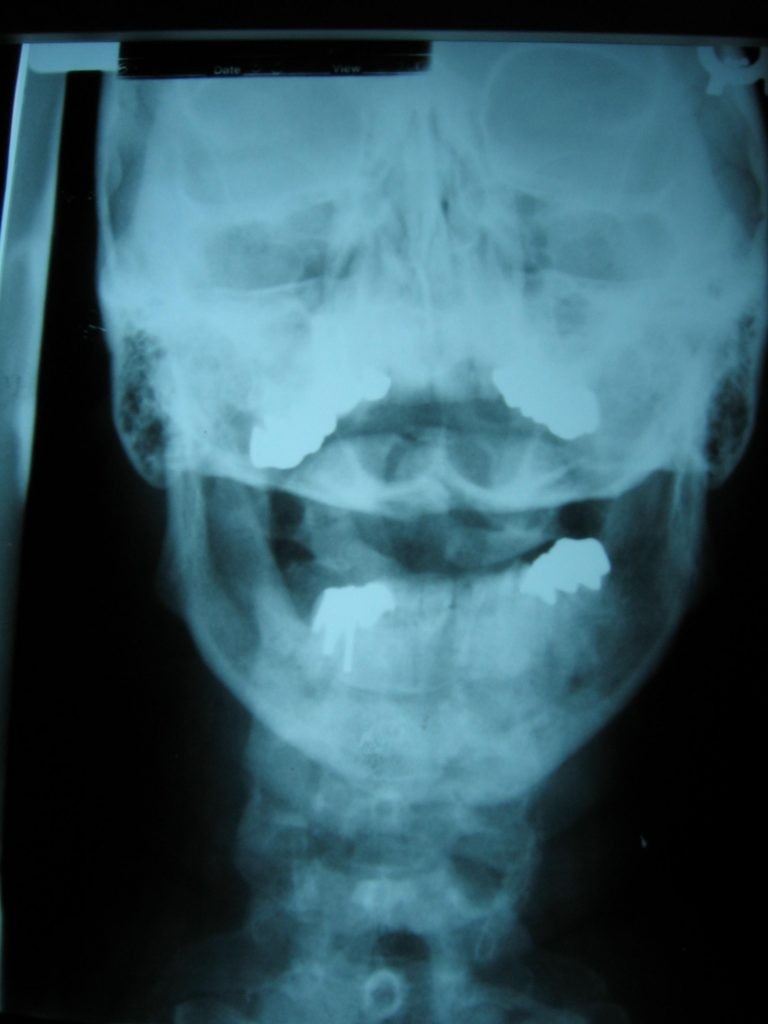

초등 세미나는 기형, 아틀라스 운동, 관절 엑스레이 촬영 및 읽기, C-1 블레어 척추 조정에 대한 블레어 박사의 혁신적인 개념으로 구성됩니다.중급 세미나는 C-2 이하 아 탈구 감지 및 교정을 가르칩니다.입체/3차원 엑스레이를 촬영하고 판독하면 관절 변위를 실제로 볼 수 있습니다.

• 블레어 박사는 비스듬한 과두 연장경으로 알려진 대서양-후두 관절을 이미징하는 독창적 인 방법을 개발했습니다.

• 관절 표면을 엑스레이 촬영하면 신체 오른쪽의 관절이 척추 왼쪽의 관절과 똑같이 형성되지 않을 수 있음을 알 수 있습니다.